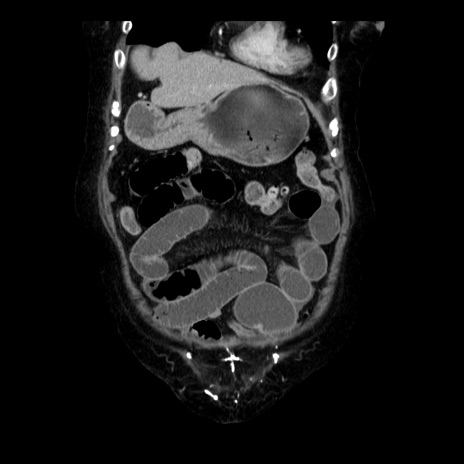

症例14(冠状断像)

【症例】 90歳代女性

【主訴】 腹痛・嘔吐

【現病歴】今朝から左側腹部痛を認めた。 経過観察していたが、嘔吐を認めたため来院。

【既往歴】 子宮癌術後

【身体所見】 意識清明、BP 127/54mmHg、P 98bpm Sp02 95%(RA)、BT 35.8°C、腹部平坦・軟腸ぜん動音聴取良好、右下腹部圧痛(+) 反跳痛なし

【データ】WBC 9800、CRP 0.46